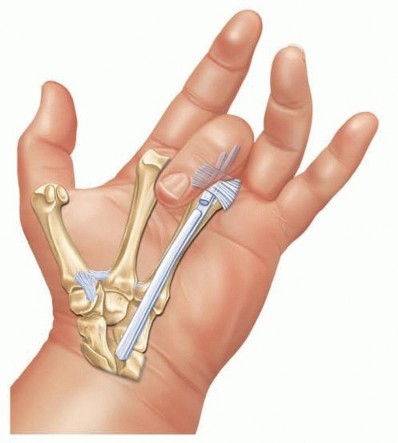

The anastomosis is performed using a Pulvertaft weave. The donor tendon is woven through the recipient tendon at perpendicular angles at least three times.

Tensioning is an art form: the transfer must be set slightly tighter than physiological resting tension, as all tendon transfers stretch post-operatively. The wrist is held in 30 degrees of extension, and the MCP joints are held in neutral. The weaves are secured with a non-absorbable, braided 3-0 or 4-0 core suture, supplemented by a running epitendinous 5-0 suture to smooth the junction and prevent adhesions.

Following the weave, the extensor retinaculum is relocated deep to the reconstructed tendons. This crucial step provides a smooth gliding surface for the new tendons and prevents them from adhering to the raw dorsal carpal capsule or the resected ulnar stump.